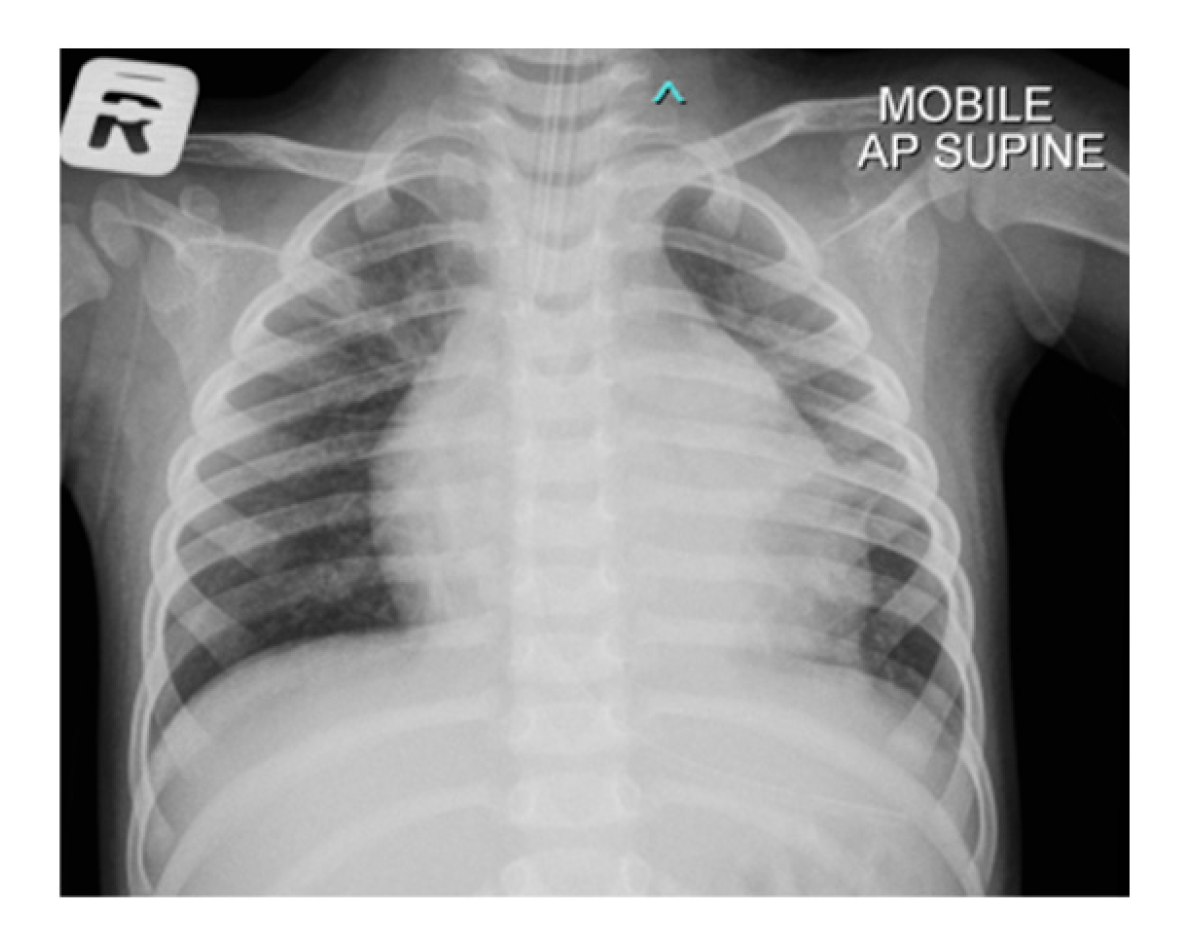

In anticipation of urgent surgical intervention for pericardial washout due to constrictive pericarditis, and to prevent cardiovascular collapse during transfer, the patient was electively intubated. Following intubation, a chest radiograph was performed, which demonstrated significant cardiomegaly with an endotracheal tube (ETT) seen in situ (Fig. 2). Computed tomography (CT) of thorax, abdomen and brain was also done and revealed bilateral pleural effusion with segmental collapse consolidation of both lower lobes. Pericardial effusion was seen and multiple mediastinal lymphadenopathy is identified, measuring 0.8 cm. Otherwise, no focal lesion such as space occupying lesions (SOL) was seen (Fig. 3).

Figure 2: Chest radiograph of the patient with cardiomegaly with bilateral plethoric lung fields.